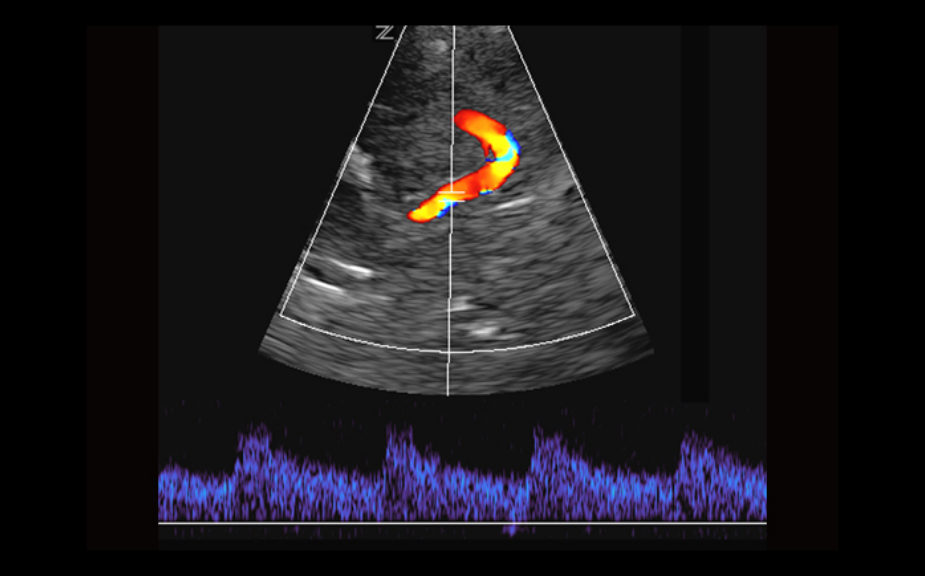

Equipped with patented, software based ZONE Sonography? Technology (ZST), the Z.One PRO provides optimally detailed B-mode and Doppler imaging for patients, regardless of body habitus, helping assure a reliable diagnosis.

- CW Doppler with auxiliary transducers

The Z.One PRO is powered by ZONE Sonography Technology, an innovative and proprietary image formation architecture that acquires and processes acoustic data up to ten times faster than conventional beamforming methods.